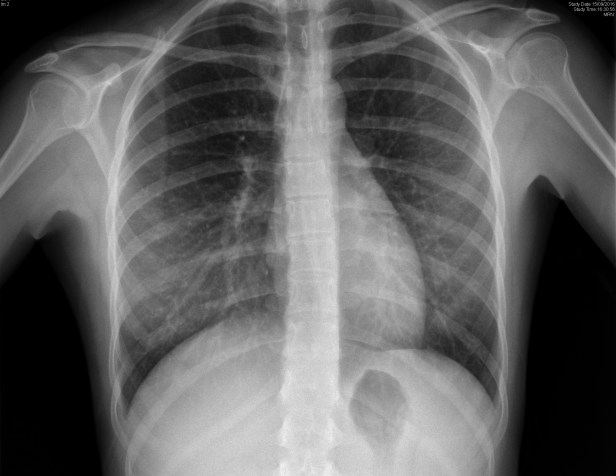

Cuando acabo de realizar la proyección PA (postero anterior) y la veo girarse es cuando veo aparecer el colgante frente a mí. Entonces encontré la ocasión de cerciorar qué efecto y qué apariciencia podría tener en la imagen. Al digitalizar la Rx PA no soy capaz de ver, a simple vista, el efecto. Pero al digitalizar la imagen de Rx lateral (más abajo) es cuando la veo sobre la piel de la paciente, a la altura del manubrio esternal. Me acerco a la paciente (que seguro leerá este artículo porque le comenté que lo publicaría) y le pido permiso para hacerle la fotografía, que pueda localizar la posición de la madera. Sio sitúa justo sobre la carina, al lado del botón aórtico.

Usando las herramientas en el visor digital (lupa, ventanas, etc..) no logro identificar al artilugio pero sin embargo sí se ve en la Rx lateral. Definitivamente, entiendo que, por la nitidez del resto de los cuerpos vertebrales, ‘está ahí, por debajo del manubrio esternal’, pero sólo logro ver la pequeña distorsión que produce al cambiar mínimamente los laterales del cuerpo de la 4º vértebra dorsal.

rx-tx-pa